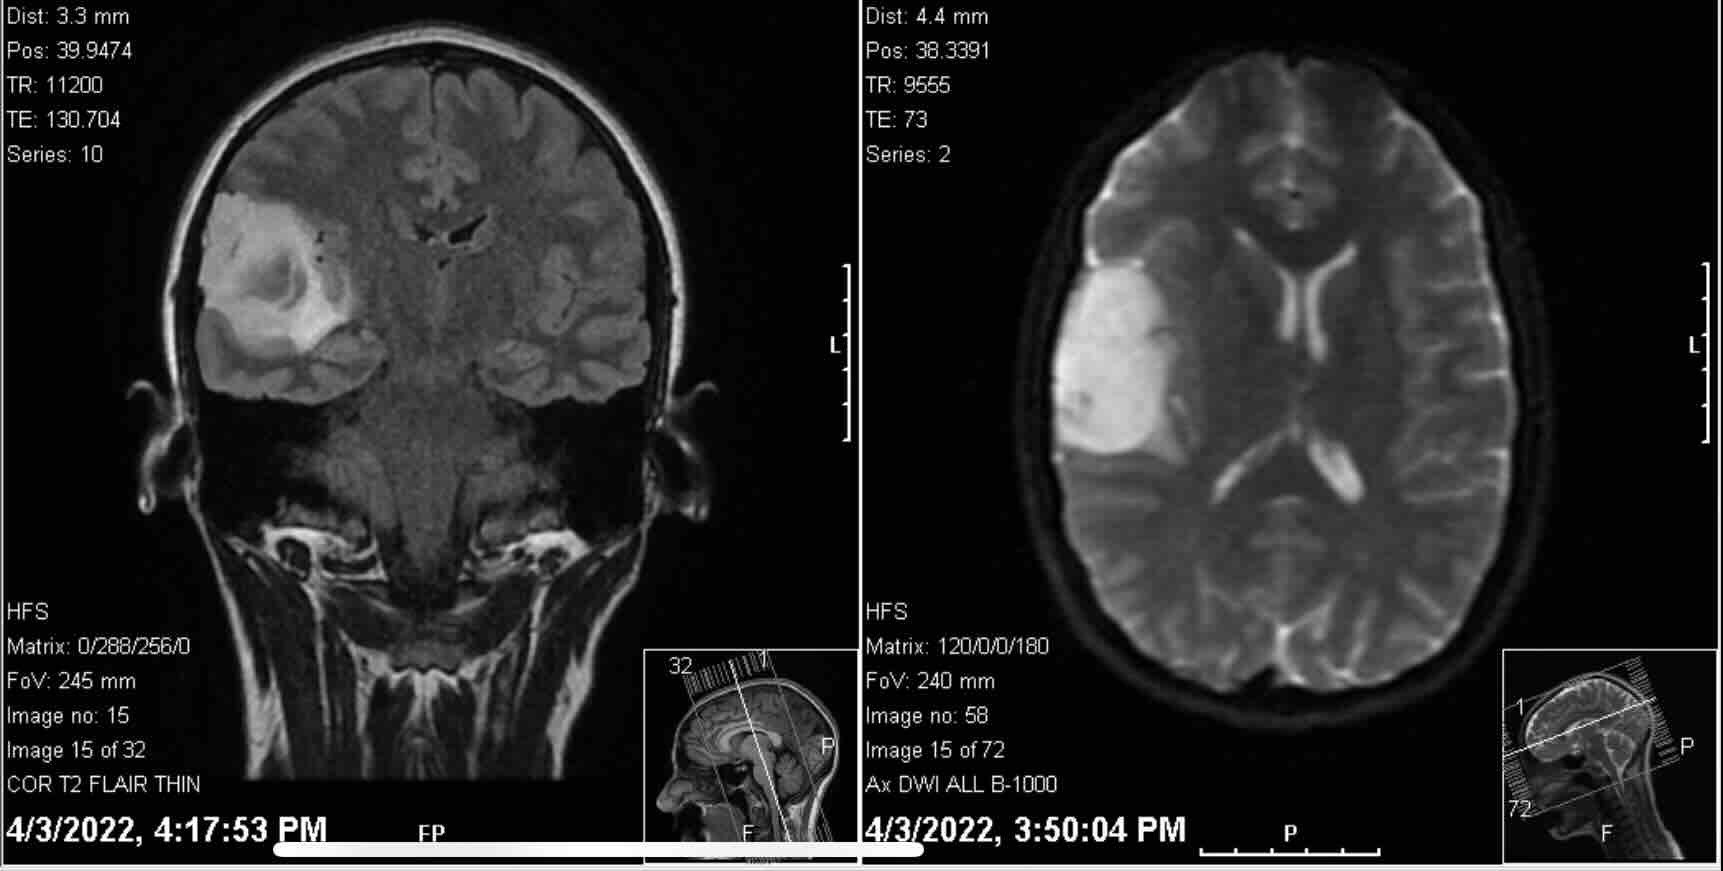

Life put up a “yield” sign for Stephanie earlier in 2022, shortly after her 30th birthday, when her primary care physician recommended she see a neurologist for some strange symptoms she had been experiencing for several months. With a history of migraines since grade school, she knew to recognize the signs of one coming on. However, in June of 2021, she woke up with a migraine that lasted for 11 days - far beyond the normal scope of her “several hour migraines” she typically experienced once a year. With this most painful migraine onset a new symptom - auditory hallucinations. As a musician, she assumed that her brain was creating this somehow familiar and always similar music in her head for some kind of reason. She just did not know what that reason was. These hallucinations, however, did not go away when the migraine did. They did not effect her daily living abilities, but did begin to increase in quantity and severity, and is what prompted her to finally see a doctor about them - they clearly were not going to go away on their own. After seeing a neurologist, EEG and MRI scans were ordered. An EEG came back normal - ruling out any abnormal brain activity. The MRI on April 3 did not provide the same hopeful news. A brain tumor was found in her right temporal lobe - the area of the brain that deals a large amount with music, rhythm, musical memories, and auditory processing - and the auditory hallucinations were then given the official name of “micro” seizure. A surgery would need to take place. Soon. Stephanie and Alex (engaged at the time) met with the neurosurgeon the following week to map out a plan and ask more questions - questions for which the surgeon would not have answers for until a surgery and biopsy was performed. He did express, however, that he assumed the tumor was benign. Stephanie and Alex’s wedding was already scheduled for May 7, and the surgeon assured them that the surgery could wait a couple more weeks and take place shortly after. Time moved forward with the hope that a surgery would occur, the tumor would be removed, and then recovery time would lead back into normal life within a couple of months. Their wedding was a Pacific Northwest dream, and exactly what the two had envisioned for their day. Their immediate family joined them in the mountains of Washington for a misty celebration. The days that followed would put the vows they made to each other into action. While still technically on their honeymoon, Stephanie was admitted into surgery for her craniotomy on the morning of May 17. Almost all of the tumor was successfully removed from the right temporal lobe - approximately 5x5 cm. The neurosurgeon said that she was the “newest newlywed” he had ever operated on.

As Stephanie was still recovering from surgery in the hospital, an oncologist visited her and Alex to let them know the tumor was more serious than they had hoped. He believed that, even before a pathology report was complete, cancer cells were present at the tumor site and that she would need to undergo rounds of chemotherapy and radiation. Shortly after, the pathology report confirmed: A Grade 3 Astrocytoma with an IDH Mutation. Brain Cancer. A disease that has no cure, and a tumor that that doctors said will grow back. Stephanie’s oncologist laid out a plan for treatment - “to buy time” - so that, hopefully, research will progress before tumor regrowth does occur. She is currently undergoing her first round of treatment and will finish soon: 6 weeks of simultaneous chemotherapy (every day) and radiation treatments (5 days/week). After this round is complete, she will have a month to recharge before beginning 6-12 more months of chemotherapy treatments at a higher dosage. She will continue receiving MRI scans on a very regular basis to keep a close watch on the state of the tumor.